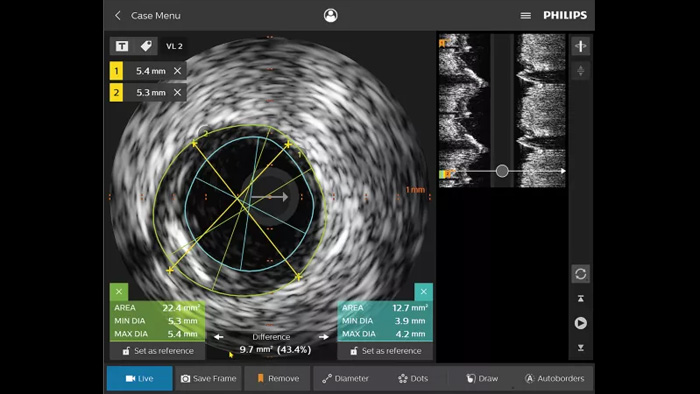

Intravascular ultrasound (IVUS) is a catheter-based imaging technology that allows physicians to visualise blood vessels from the inside out to aid assessment of presence and extent of disease. IVUS helps to decide, guide and confirm the right interventional treatment for each patient.

IntraSight provides more information through iFR/FFR and IVUS modalities in conjunction with the angiogram - controlled table side on the touch screen. It is built on a foundational platform capable of quickly adding new innovations to your lab.